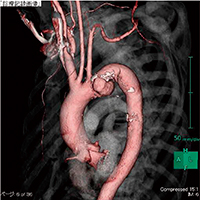

■胸部大動脈瘤におけるステントグラフト内挿術

3DCT画像 |